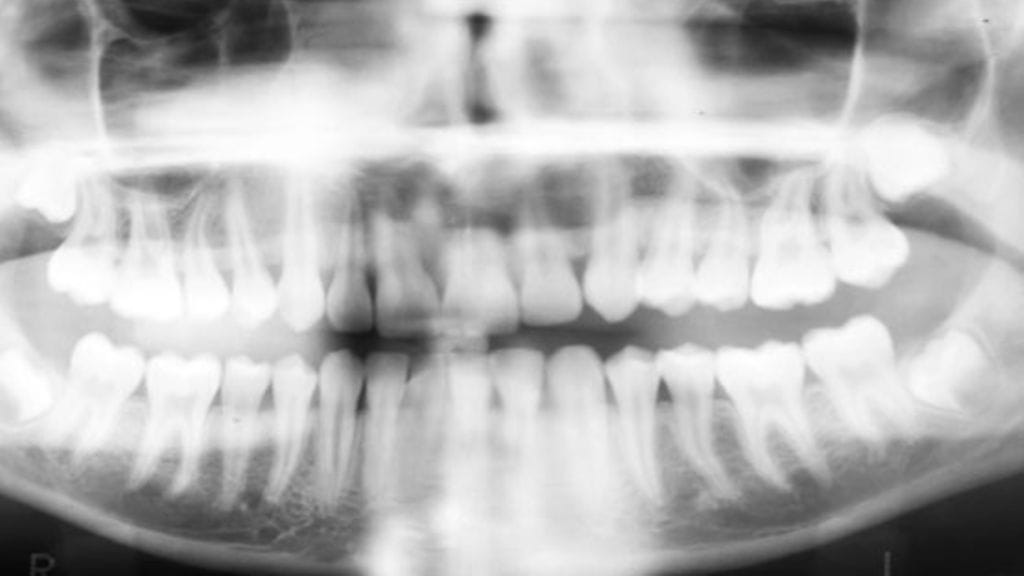

Kun ihmisen henkilöllisyydestä pitää saada tietoa, kannattaa katsoa hampaisiin.

Vaikka vertailuaineistoa ei olisi, jo hammas itsessään kertoo paljon.

– Kuolleen henkilön hampaille tehtävien mikroskooppitutkimusten kautta avautuu paljon tietoa. Kauaskin historiaan ulottuvissa aineistossa hampaiden kovakudoksista voidaan tehdä alkuaineanalyysejä. Hampaathan ovat elimistön kovimmat kudokset: ne säilyvät, vaikka luut olisivat jo kadonneet.

Iänkin pystyy selvittämään.

– Jos hampaat ovat vasta kehittymässä, ikämääritys voidaan suorittaa varsin täydellisesti. Valmiissakin hampaissa kuluminen kertoo paljon henkilön iästä.